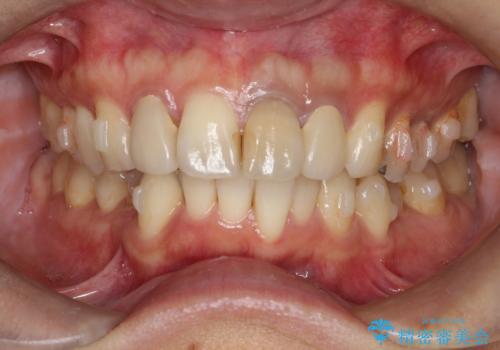

- 全体的なガタガタと前歯をきれいにしたいとのことで来院されました。

下の歯は重度のガタガタがあり、上の前歯は何本かが神経の治療がしてある状態でした。

インビザラインにて歯並びを整え、上顎の前歯にセラミックを装着する計画としました。